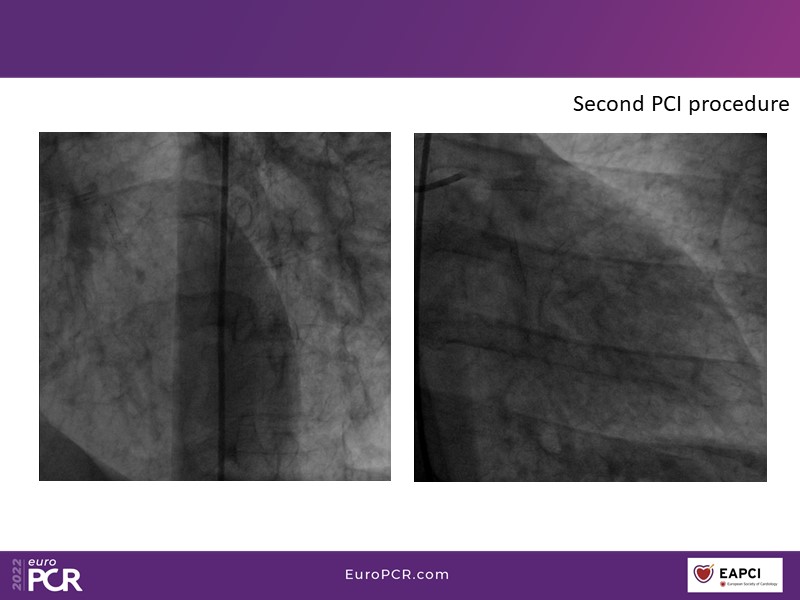

This EuroPCR 2022 session aims to show, based on real-life cases, that even complex coronary disease can be treated without the need for permanent coronary stents. Learn how to prepare the vessel, deliver the therapy, and assess immediate outcomes after "DCB-alone" PCI, discuss de novo, small vessels, and in-stent restenosis cases with follow-up, define what may be an optimal long-term result, refresh the scientific bases, and understand the clinical benefits and safety of paclitaxel DCBs.

- To know how to prepare the vessel, deliver the therapy and evaluate the immediate results after "DCB-alone" PCI

- To discuss de novo, small vessels and in-stent restenosis cases with follow-up and define what may be an optimal long-term result